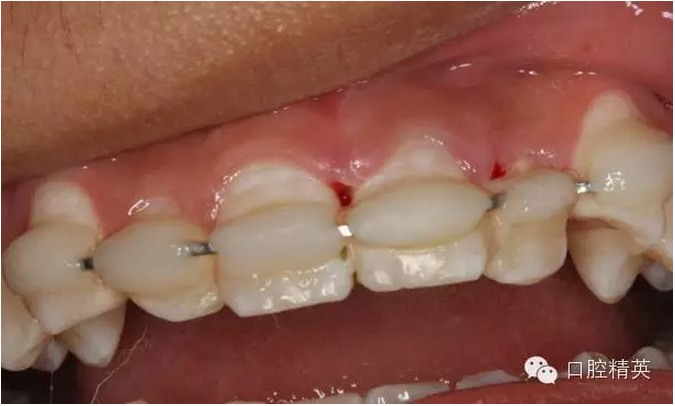

圖6.固定一個(gè)月后的唇側(cè)影像,牙齦及粘膜正常?;颊邿o(wú)任何自覺(jué)癥狀。

圖7.腭側(cè)口內(nèi)像,齦乳頭水腫消失

圖13.拋光完畢的牙面,齦乳頭色澤正常,無(wú)牙周袋。21不松動(dòng)